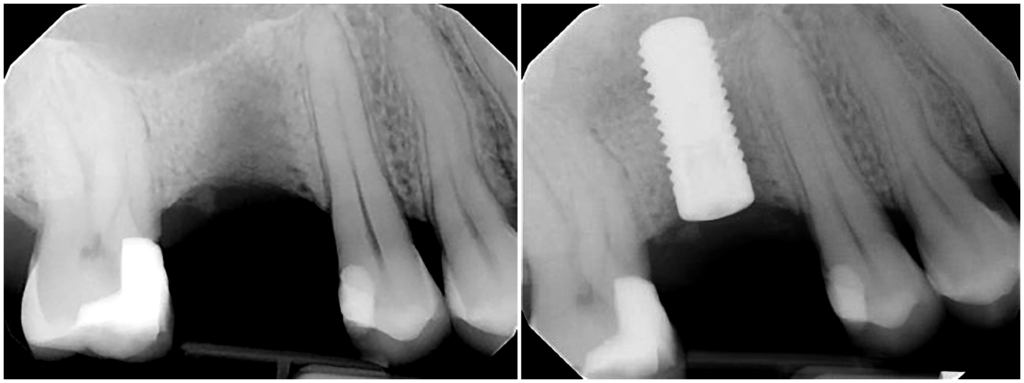

With 3D scanning, you can virtually plan an entire case before you actually do it, foreseeing problems and learning what may or may not work. This allows a perfect path to be created for the implant, avoiding anatomical features that have been identified with a CBCT scan and ensuring enough space will remain around the implant in all three dimensions. To reflect this perfect path, a surgical guide can be printed to be used in surgery.

In spite of this, having knowledge and experience in analog surgical planning and placement is necessary, allowing the clinician to better understand when and how to manipulate bone to optimize primary implant stability and to be able to navigate and manage intrasurgical challenges or complications. Expertise and experience cannot be replaced with guided surgery.